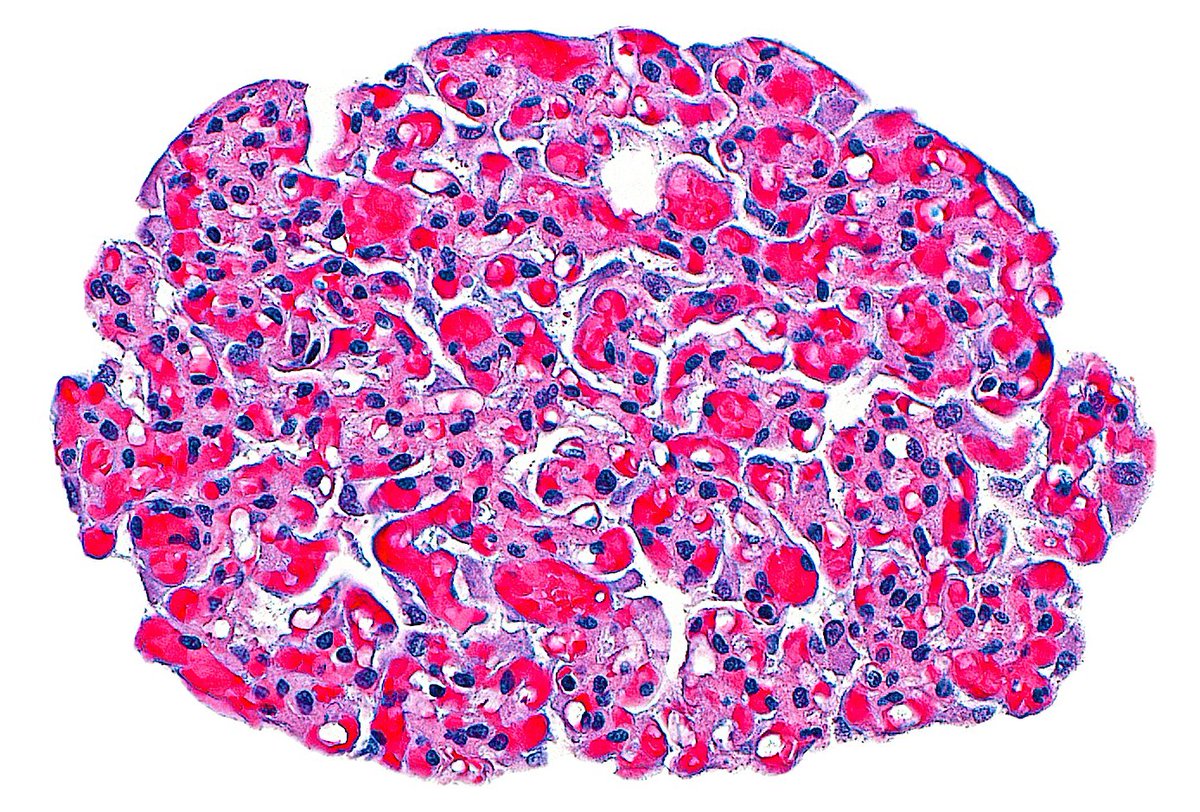

π¬π· Fallopian Tube.. from a mile above! βοΈ (Super low power view) ~ #Pathology #Histology #GYNpath #PathArt

4

16

116